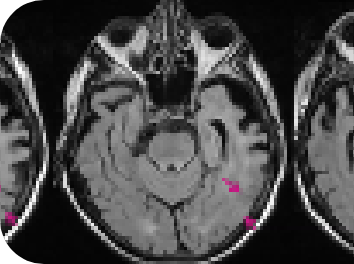

View a Case-Based Learning video on ARIA, presented by neuroradiologist, Dr Jerome Barakos. Through case examples, this on-demand video aims to familiarize you with ARIA and provide you with practical knowledge of how to detect, diagnose and differentiate ARIA from other pathologies in clinical practice.